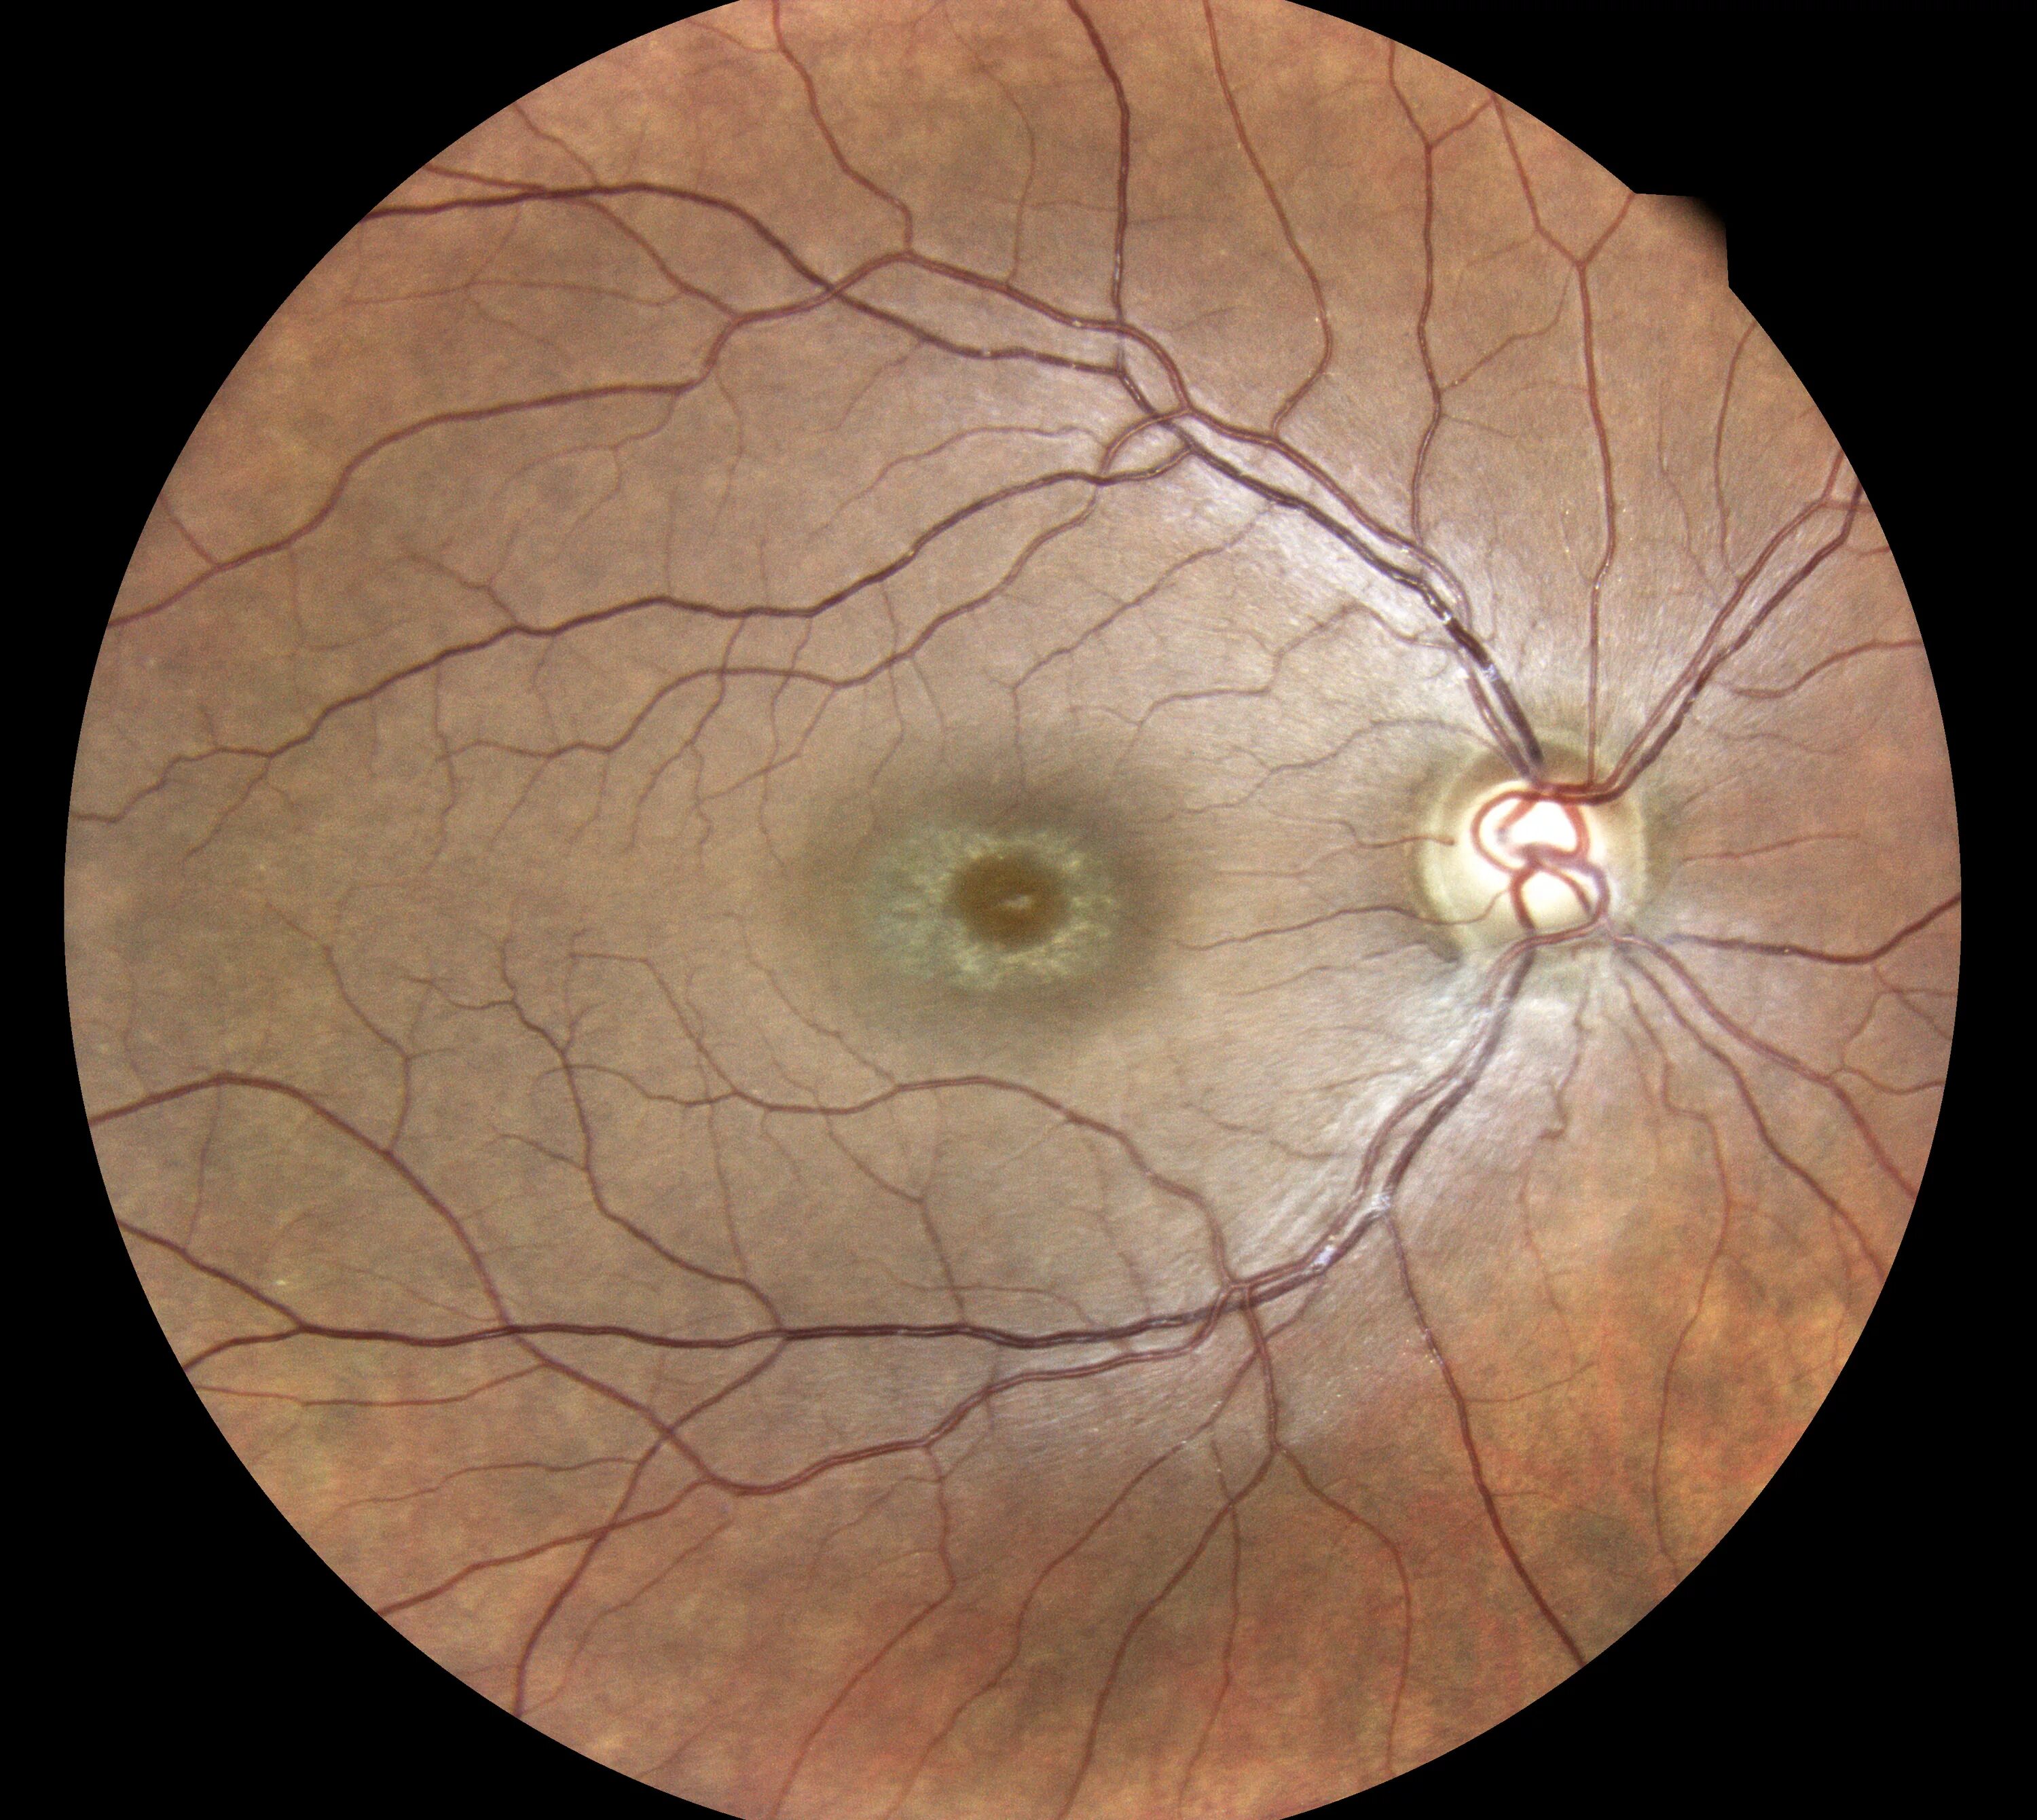

Макула